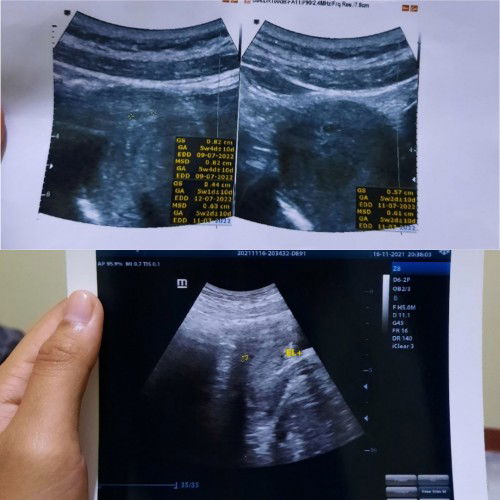

MasyaAllah, memang kuasa Allah gak ada yg tahu🥺 Padahal di tanggal 10 Nov 21 baru cek kehamilan dan dinyatakan hamil 5 minggu, lalu di tanggal 16 nya ternyata si dedek lebih milih keluar sendiri tanpa bikin orang tuanya ngerasa sakitnya di kureta🥲 Btw waktu itu aku masih kerja, jadi mungkin di dedek nya gak kuat dibawa kerja, jadinya ya dia milih keluar dengan sendirinya. Memang Allah Maha Baik & Maha Tahu apa yang terbaik untuk umatnya. Belajar ikhlas & sabar nerimanya walaupun di awal² sakit banget perasaan karena nunggunya hampir 1tahun pernikahan🥺 Tapi aku percaya Allah tahu kapan waktu yang terbaik untuk umatnya, dan alhamdulillah sekarang aku sudah diberi kepercayaan lagi sama Allah, walaupun jaraknya memang agak lama, tapi Allah pasti memberikannya di waktu yang tepat. Dan skrg aku memutuskan untuk berhenti kerja karena dokternya bilang kalau pernah ada riwayat keguguran sebaiknya pada saat hamil nanti bedrest saja untuk jaga² supaya janinnya lebih kuat. Yuk semangat buat para bumil yang masih TM1, yang lagi merasakan pusingnya, enegnya, mood swing nya, dll. Semoga kita bisa ngelewatinnya, aamiin..